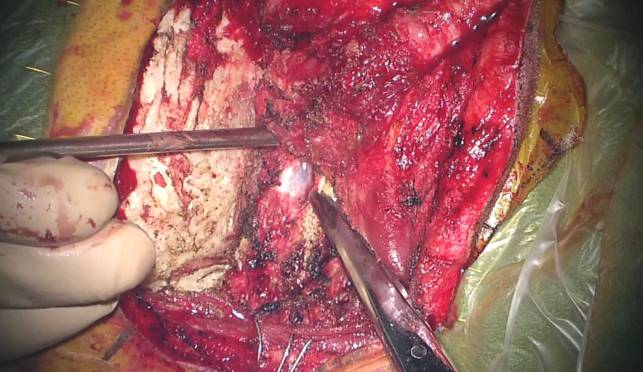

图12. 笔者通过切除外侧枕下骨质并最小化磨除枕髁来增加显露(上二图)。靠近枕髁外侧通常有一个导静脉,这是一个有用的解剖标志。这一板障内静脉会导致相当程度的出血,但是用骨蜡或者明教海绵填塞能比较容易控制。笔者沿着髁后导静脉进一步去除枕骨大孔缘并磨除枕髁后方的皮质骨。这一操作足以提供合适的到达脑干腹侧的手术通道(下图,箭头指示枕髁切除范围恰好终止于椎动脉入硬膜处的上外侧)。本质上来说,移除枕髁后内侧30%或以内的骨质通常满足到达颅颈交界区前方的需要。C1侧块关节突上方切除至恰位于椎动脉入硬膜处外侧。

如果绝对需要更广泛的枕髁切除,术者必须防止舌下神经在其通过枕髁前1/3上部时被损伤。

C1侧块关节突上部也有可能需要部分切除。枕髁切除一半或以上时会导致生物力学不稳而需要枕颈融合。

图14. 术中图片显示通过最小的枕髁切除充分显露右前外侧的枕大孔区脑膜瘤(上图)。C1神经根和副神经的上1-2个脊神经根(上图-位于剪刀头端)可能会在显露这样的大肿瘤时被切断。沿肿瘤包膜后极向外侧移动副神经。最后的切除结果也被展示(下图)。在下图中你可以看见,这种有限枕髁切除理念的经髁入路足以到达颅颈交界区腹侧。